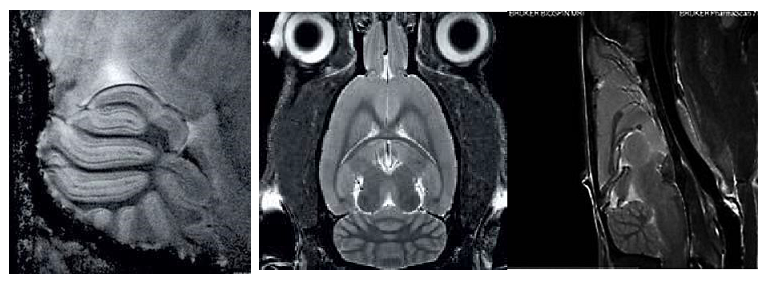

1、高分辨率神經(jīng)解剖結(jié)構(gòu)

布魯克結(jié)合超高磁場(chǎng),先進(jìn)的相陣控線圈和譜儀技術(shù)提供完美品質(zhì)的結(jié)構(gòu)形態(tài)成像。超高空間分辨率可以顯示精細(xì)的顯微組織結(jié)構(gòu)。領(lǐng)先的磁共振成像技術(shù)在超高磁場(chǎng)下提供完美的對(duì)比度。

磁共振成像低溫探頭增加150%的靈敏度,清晰顯示小鼠腦部細(xì)胞層狀結(jié)構(gòu)(小腦的顆粒層和浦肯雅細(xì)胞層),空間分辨率達(dá)到 50μm:

9、猴腦成像

靈長(zhǎng)類(lèi)動(dòng)物是我國(guó)腦科學(xué)計(jì)劃中關(guān)鍵實(shí)驗(yàn)動(dòng)物,對(duì)理解大腦的功能運(yùn)轉(zhuǎn)有極大的作用。可以實(shí)現(xiàn)小型絨猴靈長(zhǎng)類(lèi)動(dòng)物成像,大大提高空間分辨率。

絨猴的大腦成像: